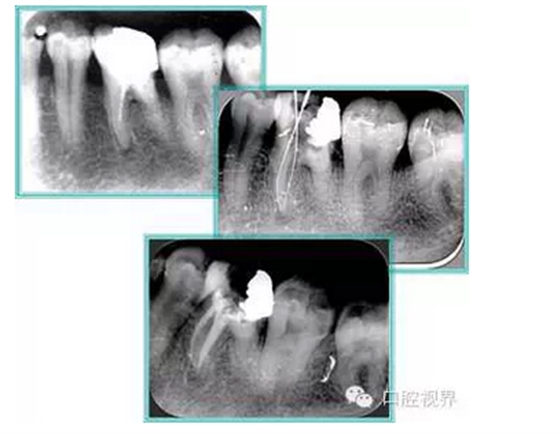

根管治療常見問題有丟失工作長度、偏離正常的解剖形態(tài)和不適當?shù)母茴A備。本節(jié)主要介紹丟失工作長度。一、堵塞(blockage)

( 1 )定義:堵塞指根管內(nèi)的阻塞物阻擋器械到達根尖孔。

( 2 )原因:牙本質碎屑、組織碎屑、棉花、紙捻、充填物、折斷器械在根管中的堆積。

2. 牙本質碎屑

堵塞最常見的情況是銼的型號遞增過快,將碎屑向下擠入,或是對彎曲根管切割過度最終造成根尖 1/3 處碎屑過量沉積。

解決方法: ( 1 )器械換號應按梯次更換,盡量避免跳號,如 10、15、20、25、30 號依次更換。 ( 2 )NaCl 液頻繁沖洗。 ( 3 )重復使用小號銼并經(jīng)常檢驗工作長度。

二、臺階

定義:根管內(nèi)壁上人為產(chǎn)生的不規(guī)則形狀阻止器械順利進入根尖。

原因:器械沒有預彎,根向壓力過大。

右圖箭頭處示臺階形成。

解決方法: ( 1 )器械預彎。 ( 2 )若出現(xiàn)銼的螺紋擰緊,立即換用小號銼。 ( 3 )一旦到達WL,即按照從小到大順序預備根管。 ( 4 ) H銼幫助提高切割效率。